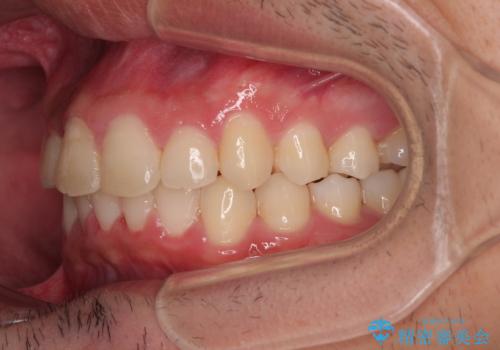

- ディープバイトと上顎前歯の突出、奥歯の咬み合わせを気にして来院された患者様です。

上顎歯列は全体的に前方位にあり、それが原因で深い咬み合わせとなり、突き上げにより上顎前歯が前方に飛び出している状態でした。

また、左右ともに上顎最後臼歯が頬側に転位している鋏状咬合となっていました。

インビザラインによる矯正治療をご希望でしたが、上顎歯列の前方位と鋏状咬合を確実に改善することを目的として、補助装置を併用することとしました。

補助装置を併用せずに治療を終える可能性はありましたが、確実に結果を得るために補助装置を活用しました。

イメージしたとおりの仕上がりとなりました。